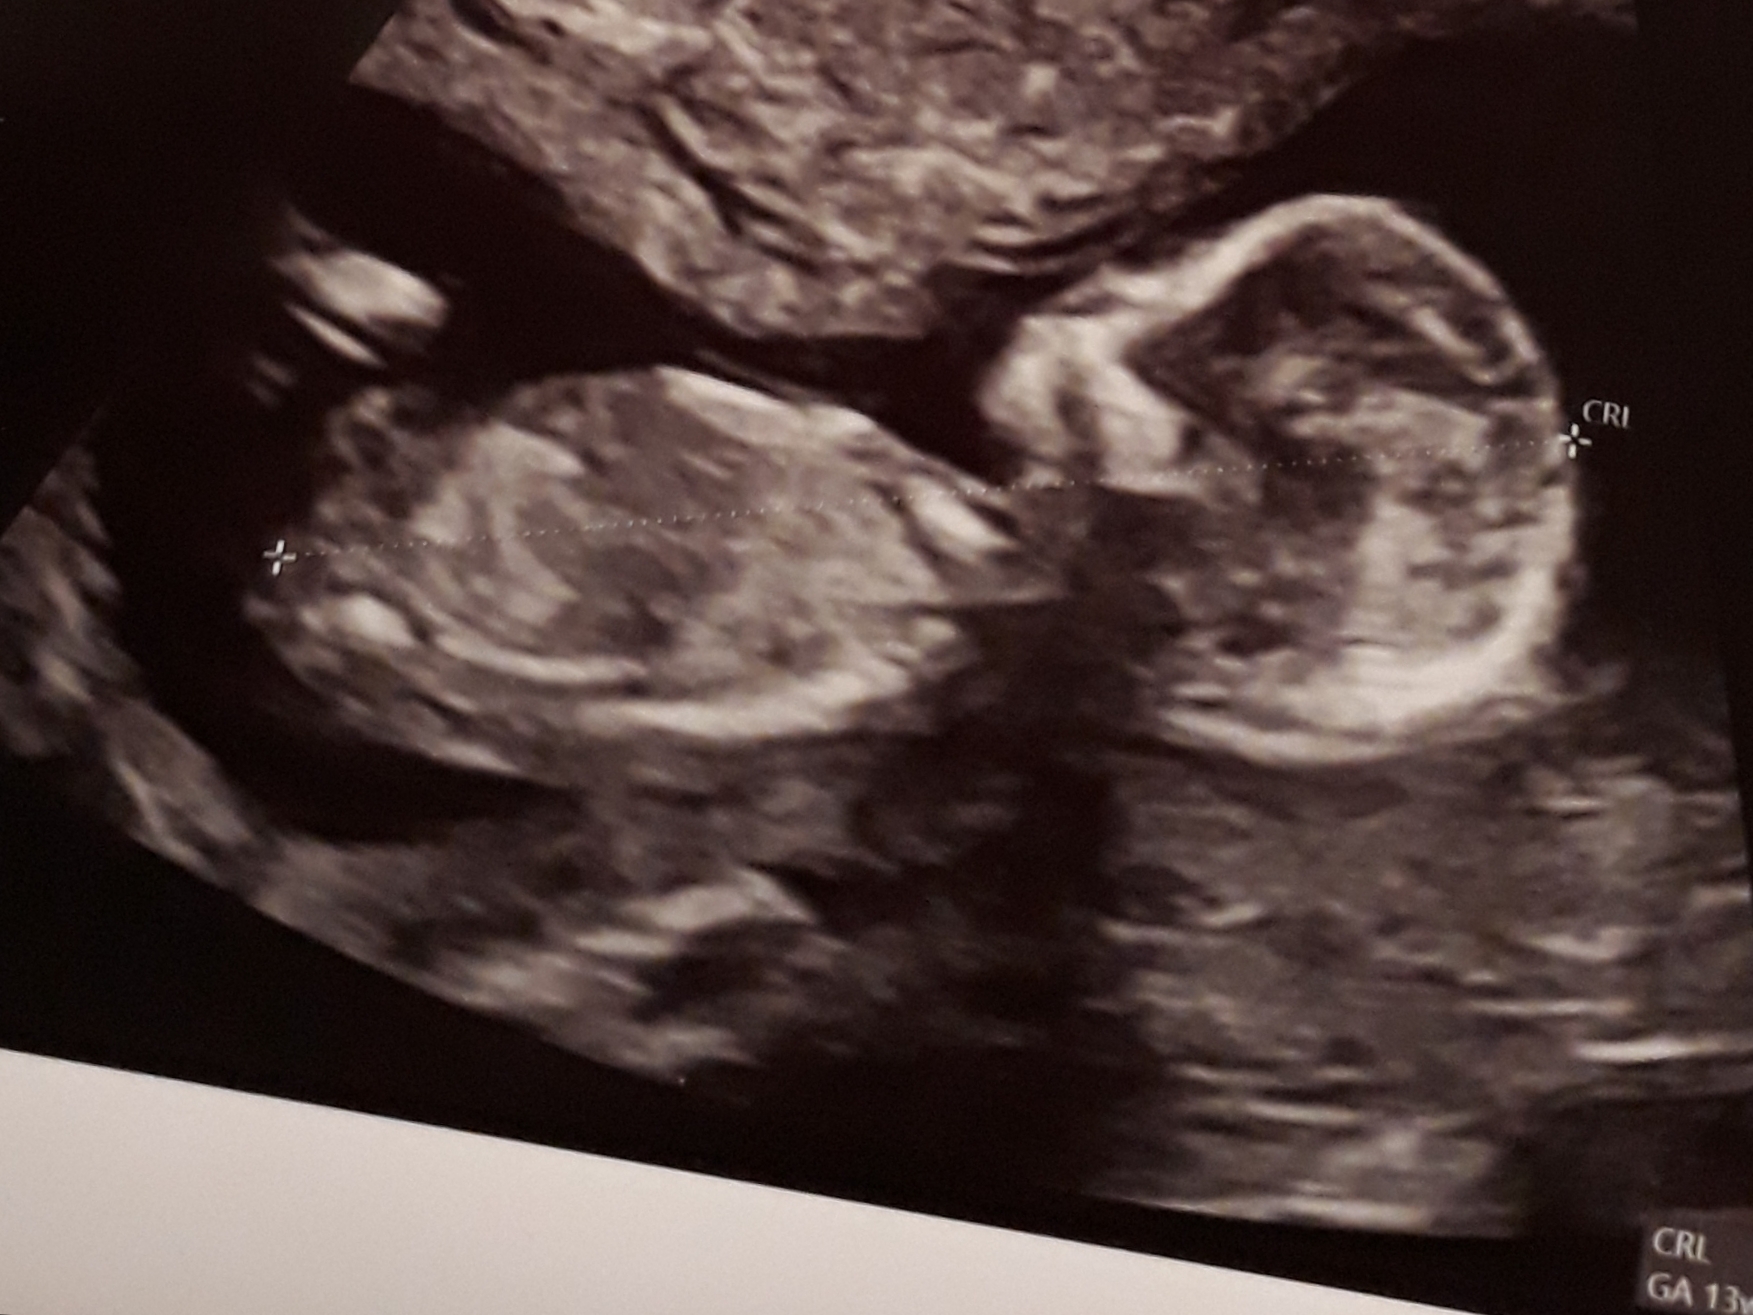

Hello, It's a boy? 😍 Thanks. His legs were up 😅

I'm not sure I can guess on this, I am worried the sticking up thing may be umbilical cord. Do you have any more?

No it's coming right out from the middle of the tummy there. That would be a baby with a penis in the middle of his stomach LOL. The nub is lower, more where that little x is for the measurement, and that has not been captured in the photo.